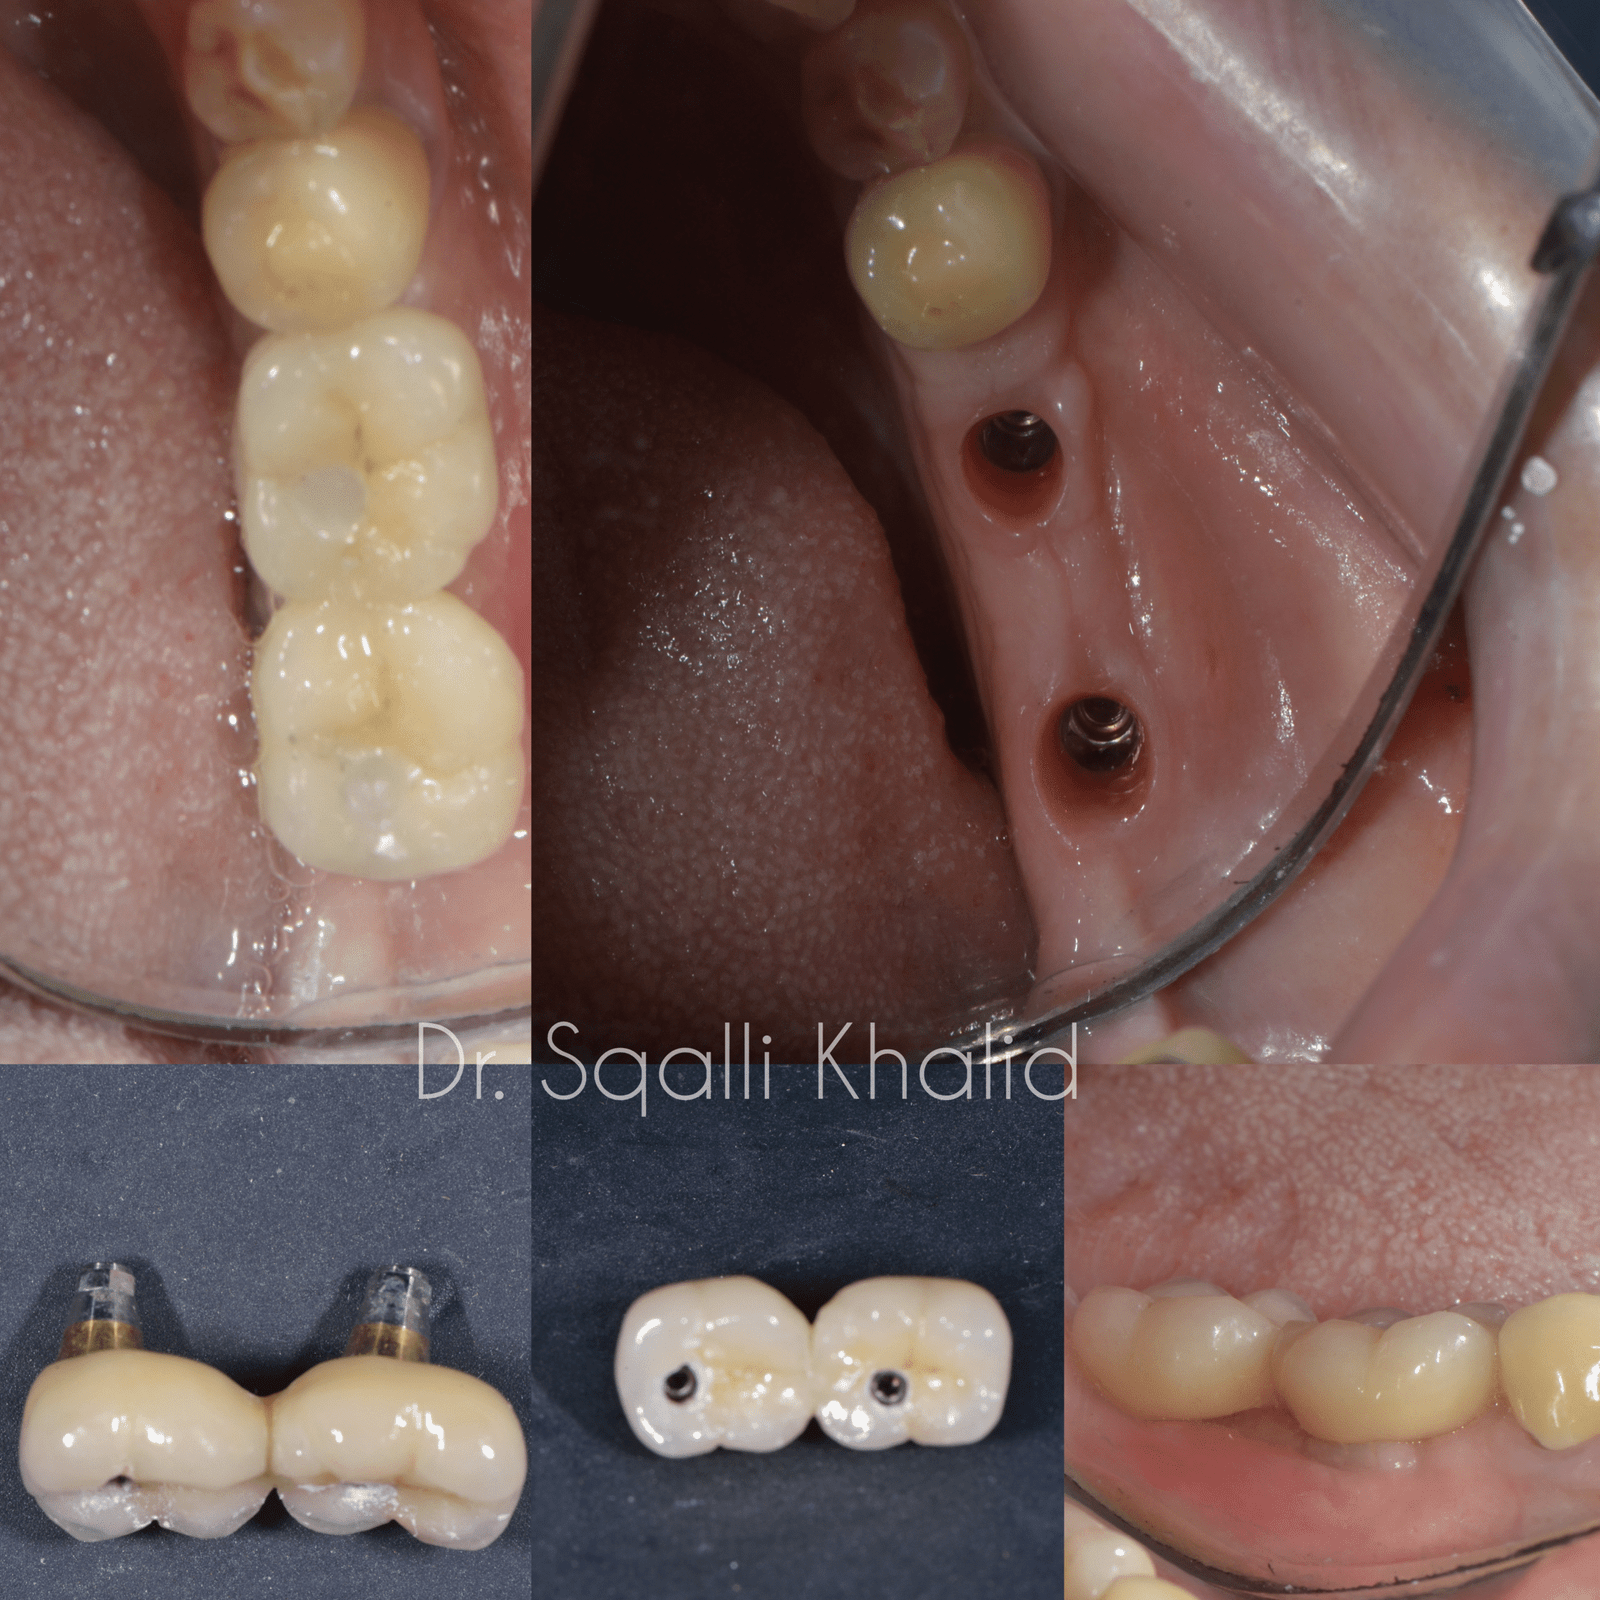

Un implant dentaire est une racine dentaire artificielle en titane biocompatible. Il est placé chirurgicalement dans l’os de la mâchoire et sert de base solide à une couronne, un pont ou même une prothèse complète.

Contrairement aux options traditionnelles telles que les prothèses amovibles ou les bridges, les implants sont fixes, stables et offrent la même sensation que les dents naturelles.